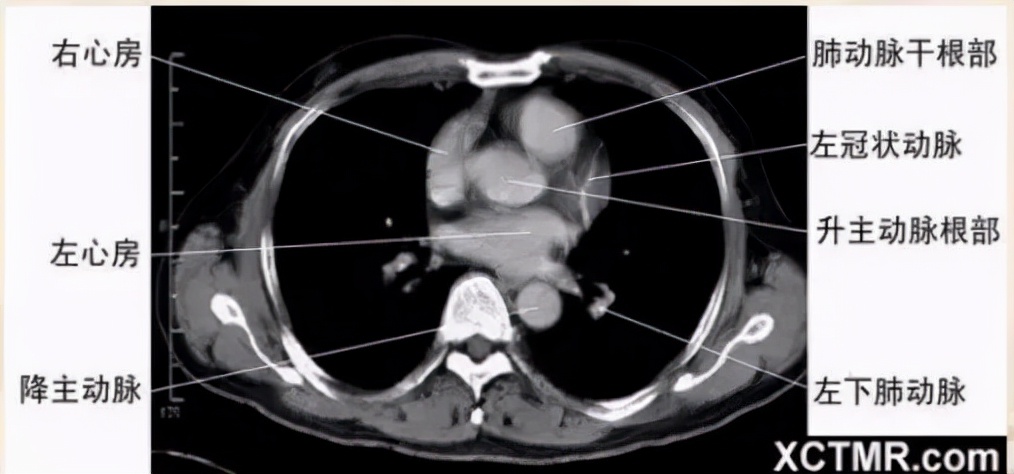

左心房层面